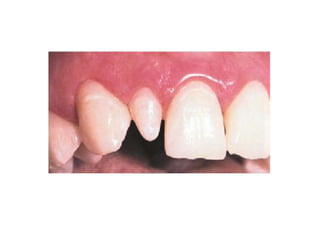

2. Missing Teeth

• Hypodontia

• Oligodontia

• Anodontia